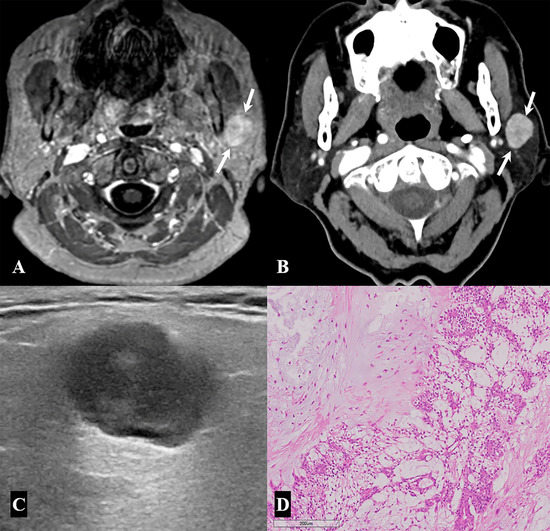

2. Materials and Methods

2.3. Assessment of Incidental Parotid Lesions: Image Analyses